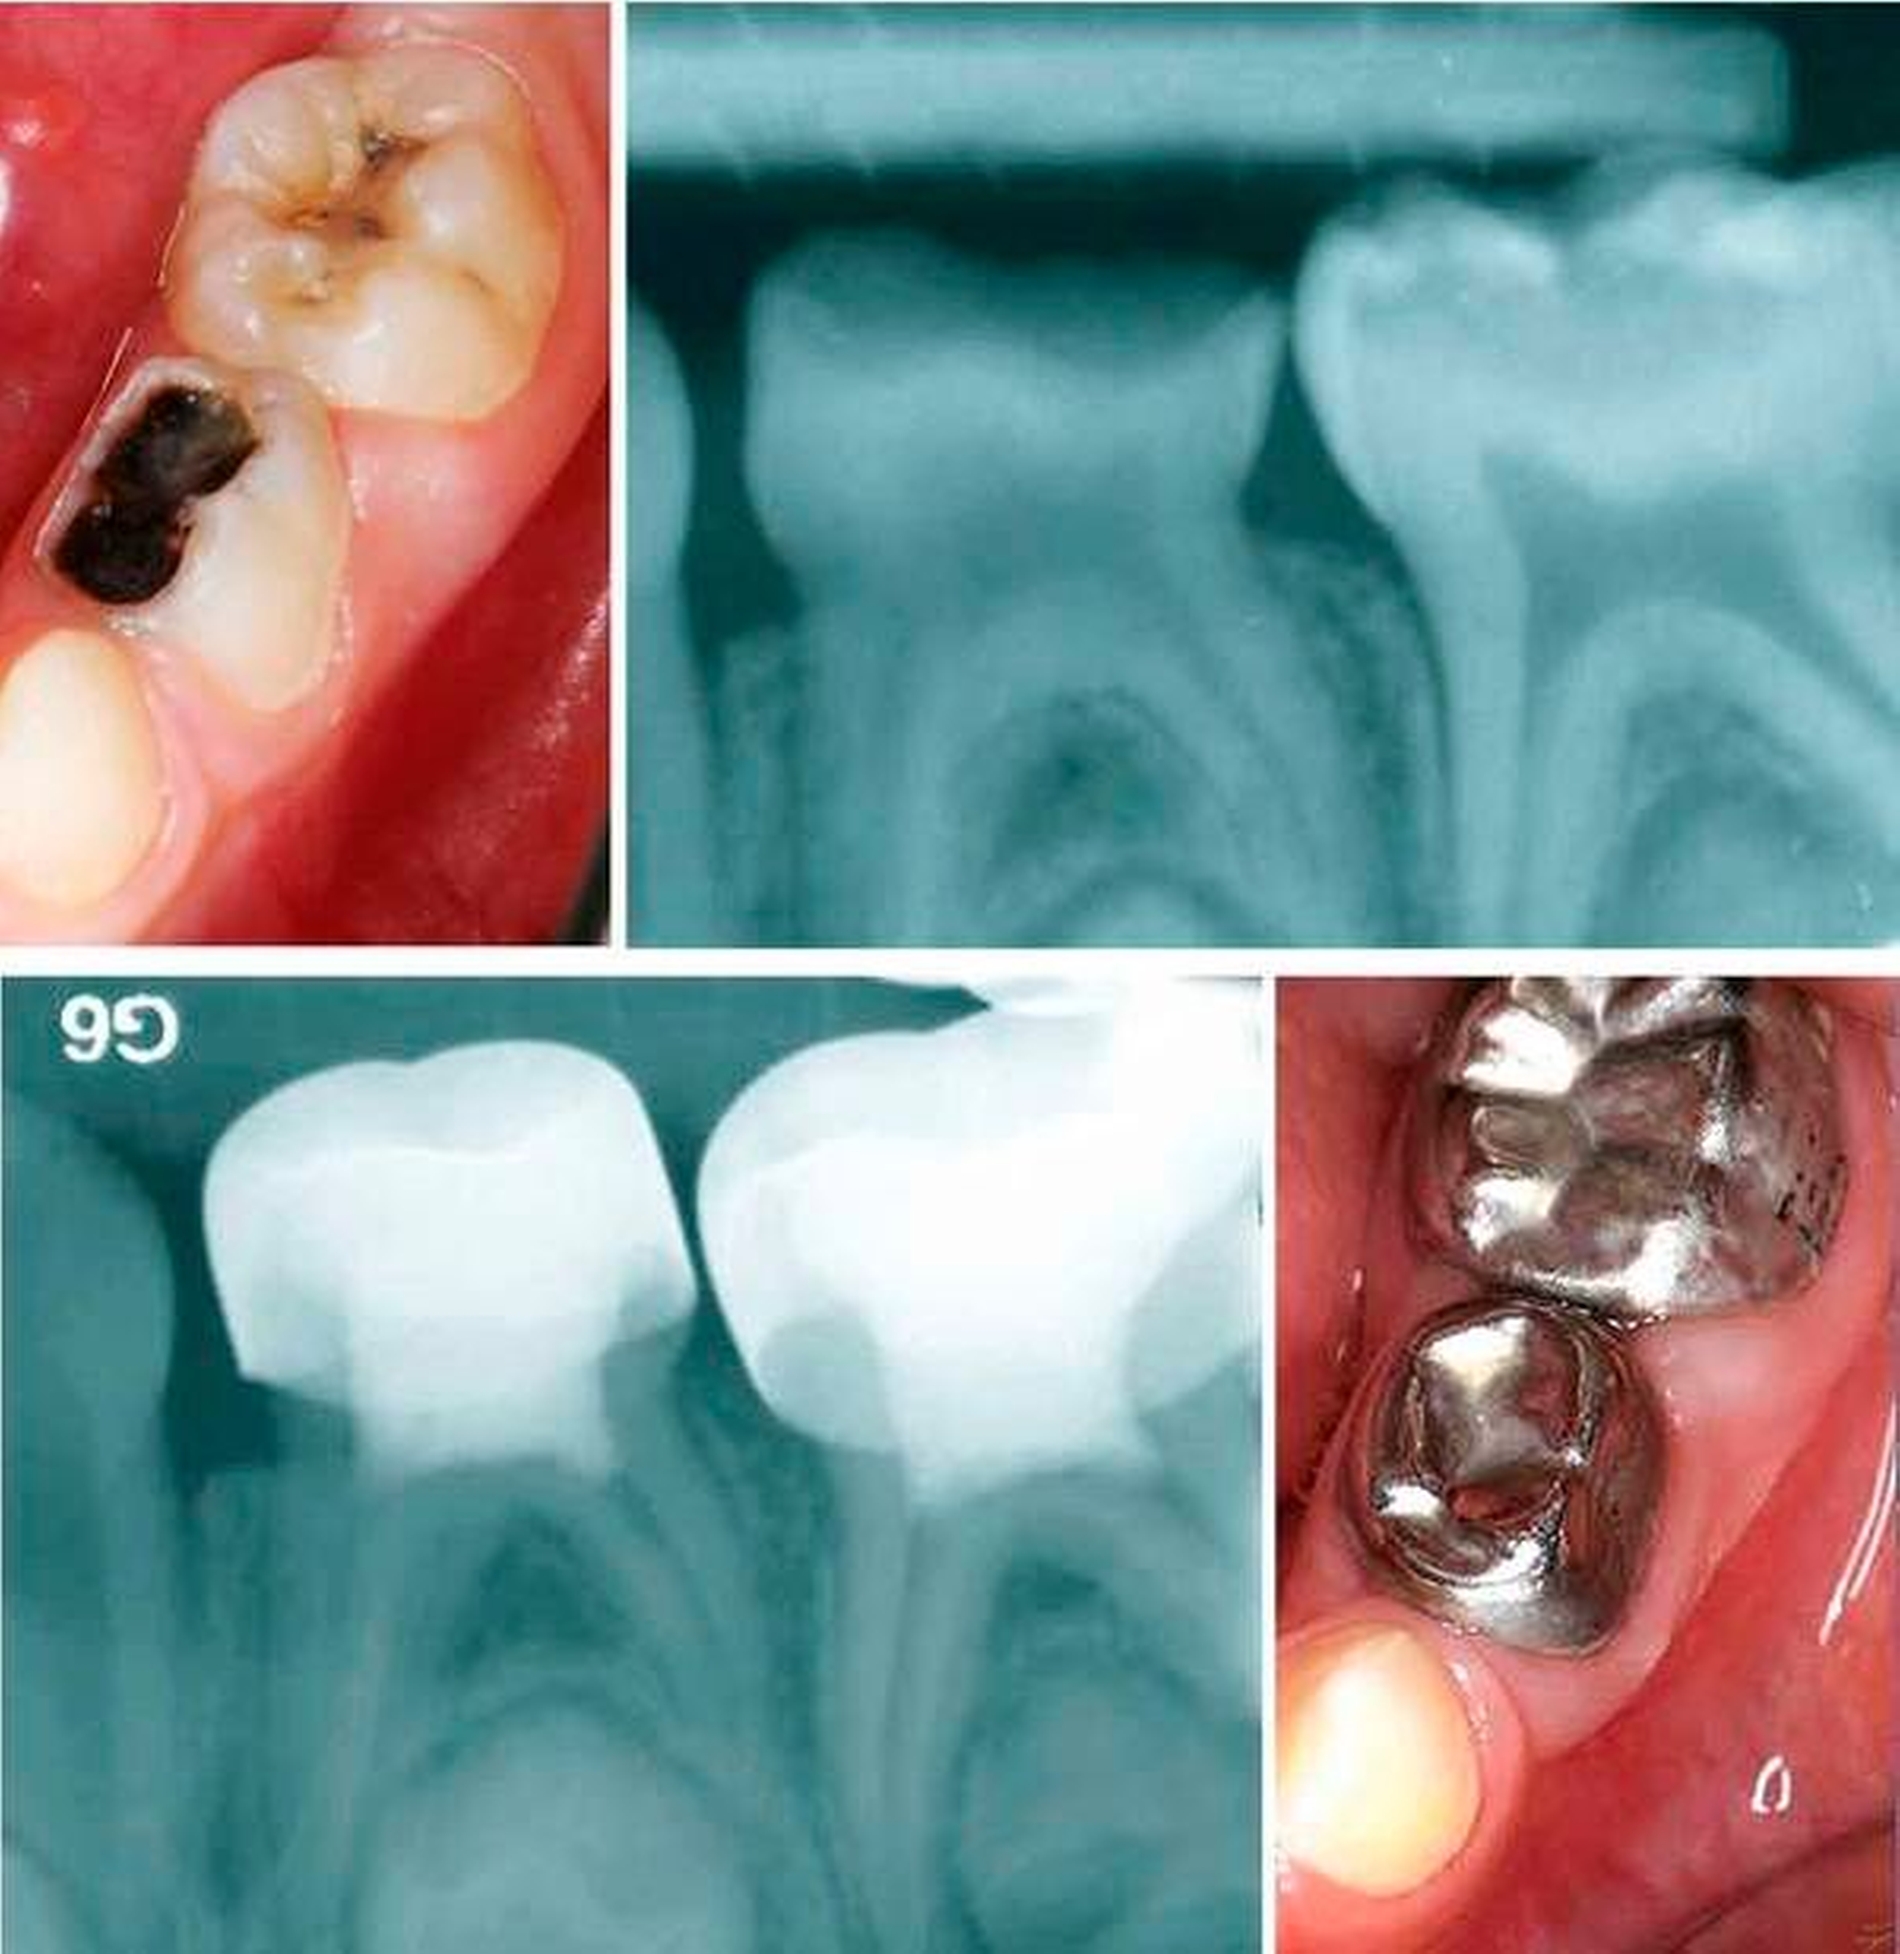

Da die Füllungstherapie im Milchgebiss sehr schnell an ihre Grenzen stößt und bei nicht adäquaten Restaurationsdefekten das Risiko eines Füllungsverlusts oder einer Sekundärkaries (Abbildung 10) besteht [Van Waes, 1993], stellt die konfektionierte Kinderkrone in vielen Fällen die einzige Möglichkeit zum Zahnerhalt dar.

Die wichtigsten Indikationen für Milchzahnkronen sind die umfangreiche Glattflächenkaries, mehrflächiger Kariesbefall, floride Karies, endodontisch behandelte Zähne, Anomalien der Zahnform und -struktur und der Erhalt des mesio-distalen Kronendurchmessers [Schulte, 1999]. Die wohl am ältesten und am weitesten verbreitete Variante ist die konfektionierte Stahlkrone für den Molarenbereich (Abbildung 11). Nach erfolgter Exkavation, eventuell durchgeführter endodontischer Maßnahme und Aufbaufüllung mittels Glasionomerzement erfolgt die Kronenpräparation. Hierfür wird der Zahn okklusal um circa 1,5 mm reduziert. Die Kontaktpunkte werden mesial und distal gelöst, die Approximalflächen stufenlos präpariert und anschließend alle Übergänge abgerundet. Die bukkal und oral gelegenen zervikalen Schmelzwülste werden nicht beschliffen, da durch diese der gewünschte Schnappeffekt erzielt wird.

Die einzugliedernde Krone sollte die mesio-distale Breite des ursprünglichen Zahns wahren und kann beispielsweise mit einem Glasionomerzement befestigt werden. Dabei können die auftretenden Zementüberschüsse noch im flüssigen Zustand mit der Multifunktionsspritze entfernt werden. Leichte Okklusionsunterschiede nivellieren sich innerhalb weniger Tage und anfängliche Spannungen direkt nach der Eingliederung oder Gingivareizungen legen sich schnell, so dass die Krone bei den Kindern gute Akzeptanz findet. Mit etwas Übung und guter Patientencompliance beträgt der Zeitaufwand für die Anfertigung einer Krone maximal zehn Minuten. Eine allgemeinzahnärztliche Praxis sollte diese Versorgungsoption in Kombination mit der Vitalamputation beherrschen, da ein Großteil der Seitenzahnkaries auf diese Art und Weise erfolgreich behandelt werden kann und der Materialaufwand gering ist. Dadurch, dass der zweite Milchmolar oft bis zum elften Lebensjahr im Mund verweilt, stellt die Stahlkrone für diesen Zahn die dauerhafteste Restauration im Milchgebiss dar. Eine Füllung im Milchzahn würde kaum acht Jahre Bestand haben.